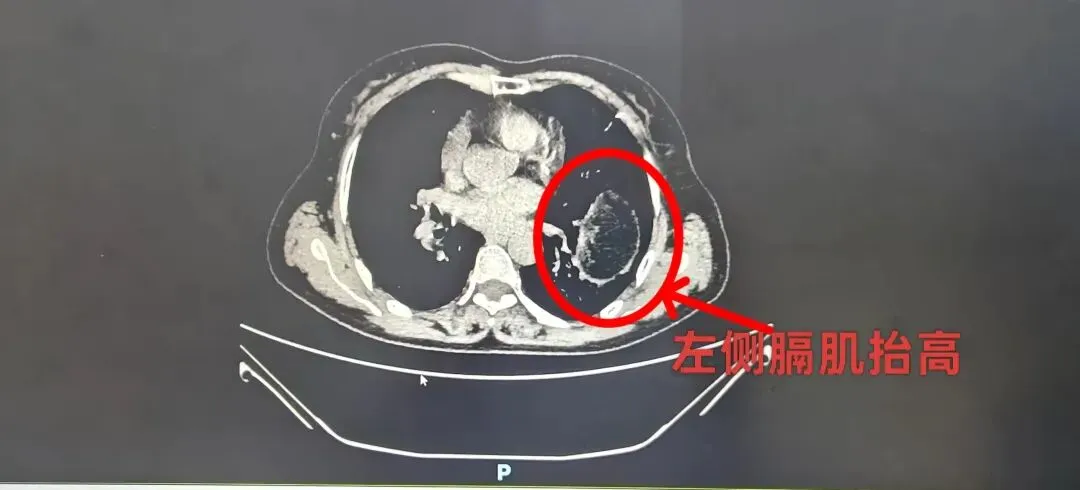

患者,66 岁女性,1 年余前无明显诱因出现上腹部胀痛,呈间歇性发作,伴随上腹饱胀不适、胸闷、气短、咳嗽等症状,无恶心呕吐、发热寒战等不适。期间患者曾辗转就诊,完善胸部薄层CT+上腹部 CT+胸部正位DR检查后,最终确诊为左侧膈膨升,且伴随左侧膈肌抬高、膈下脏器向胸腔膨隆的表现。